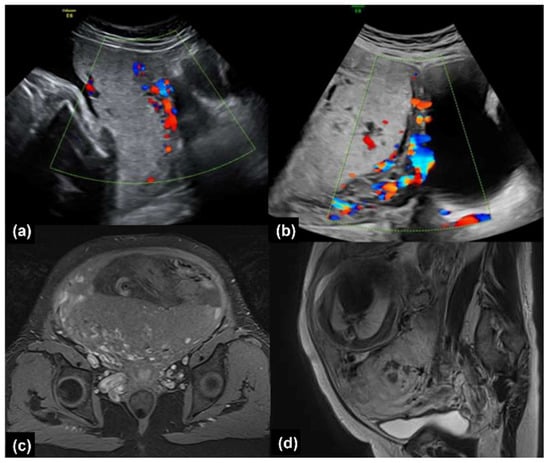

2.1.2. Clinical Findings and Diagnostic Assessment

2.2.2. Clinical Findings and Diagnostic Assessment